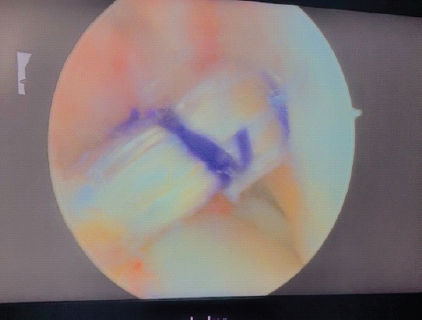

Tibial tunnel was created avoiding medial exostosis, and femoral tunnel was drilled via anteromedial portal to bypass femoral exostoses. Fixation was achieved using femoral Endobutton and tibial ‘T’ button. No intraoperative complications occurred, and arthroscopy confirmed good graft position (Fig. 4). Postoperative rehabilitation commenced on day one, and the patient progressed uneventfully (Fig. 5).

Figure 4. Arthroscopic image showing peroneus longus graft in situ after fixation.